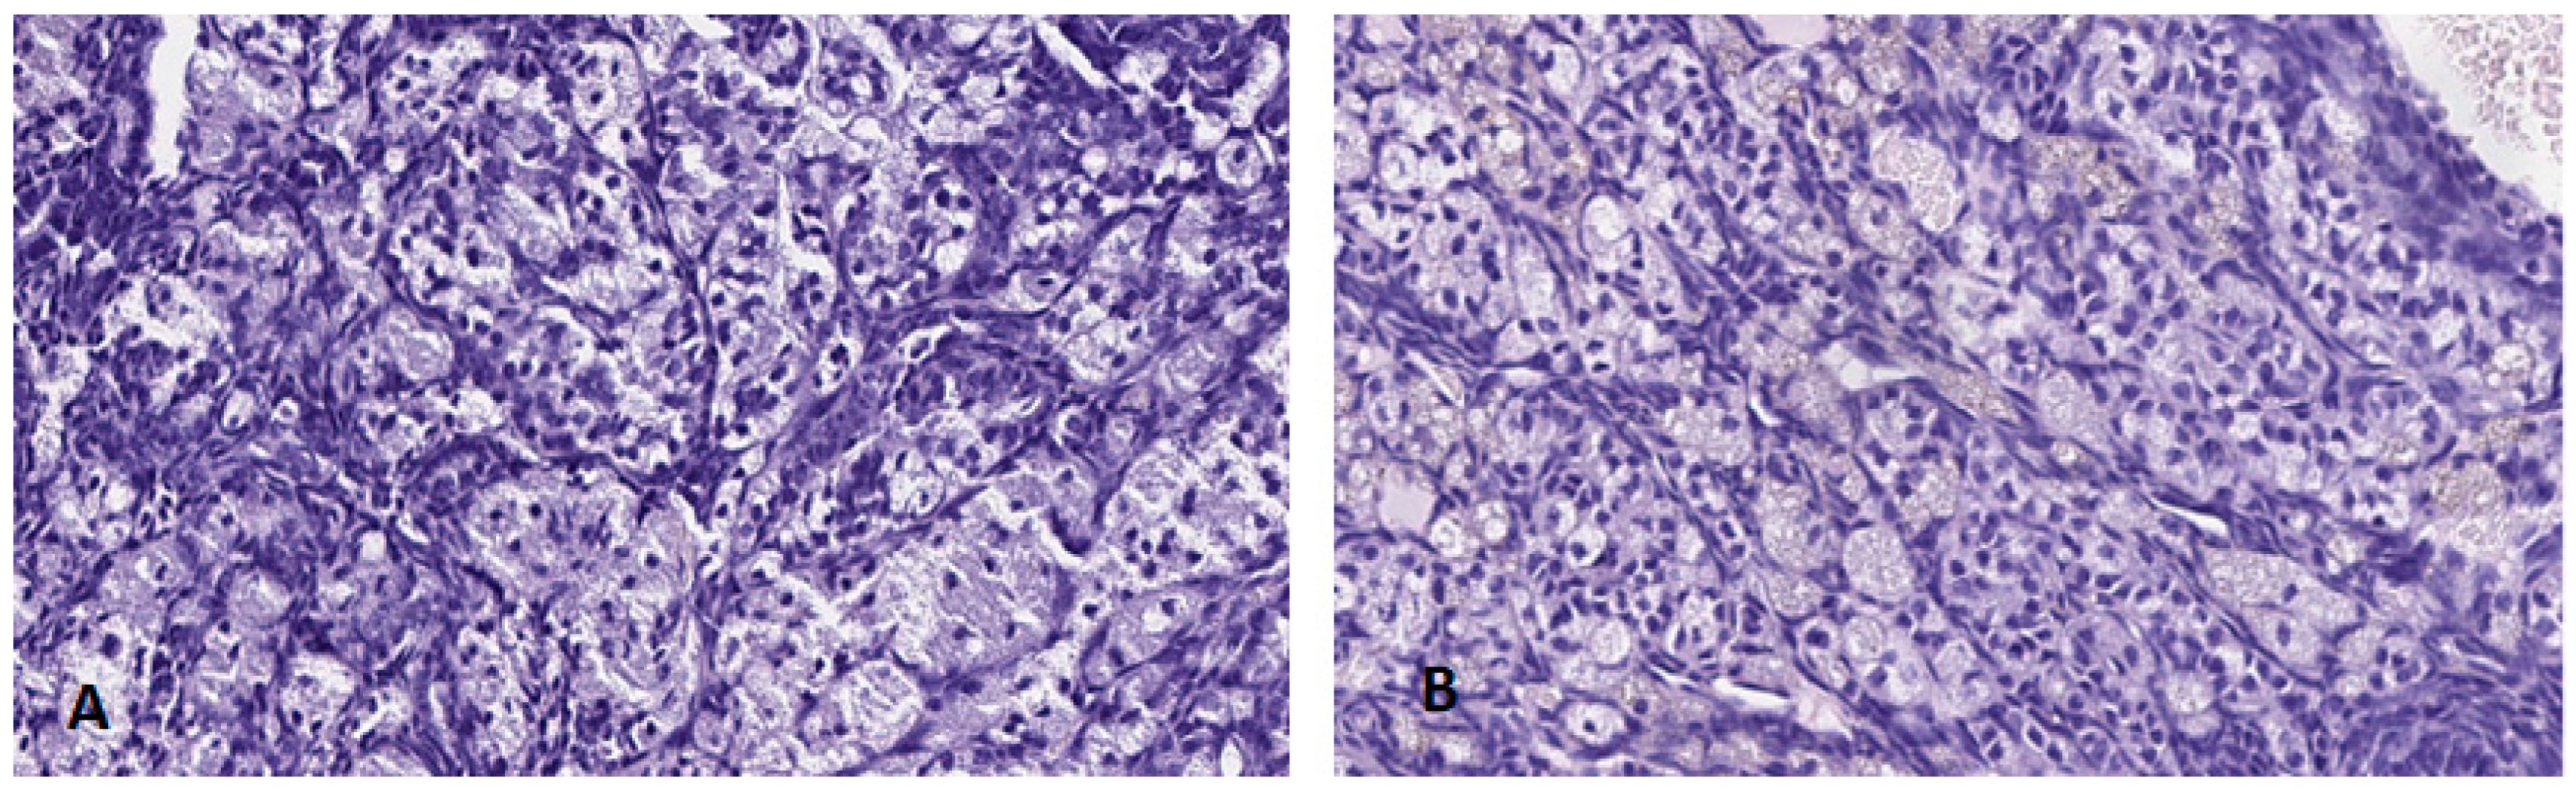

3.4.2. Ovary

Macroscopically, no lesions were observed in the morphology, colouring or size of the ovaries in any of the groups treated or in the control group.

The ovarian tissue did not present any histological alteration and none of the samples of treated females analysed showed any change with respect to control group females (Figure 10), displaying a normal architecture with follicular structures with abundant interstitial lutein cells. Similarly, a well-differentiated peri-ovarian lymphoid tissue was noted.

Figure 10.

Histological sections of ovaries in female mice from the control group (A) and group 5 (B), (H-E 20×).